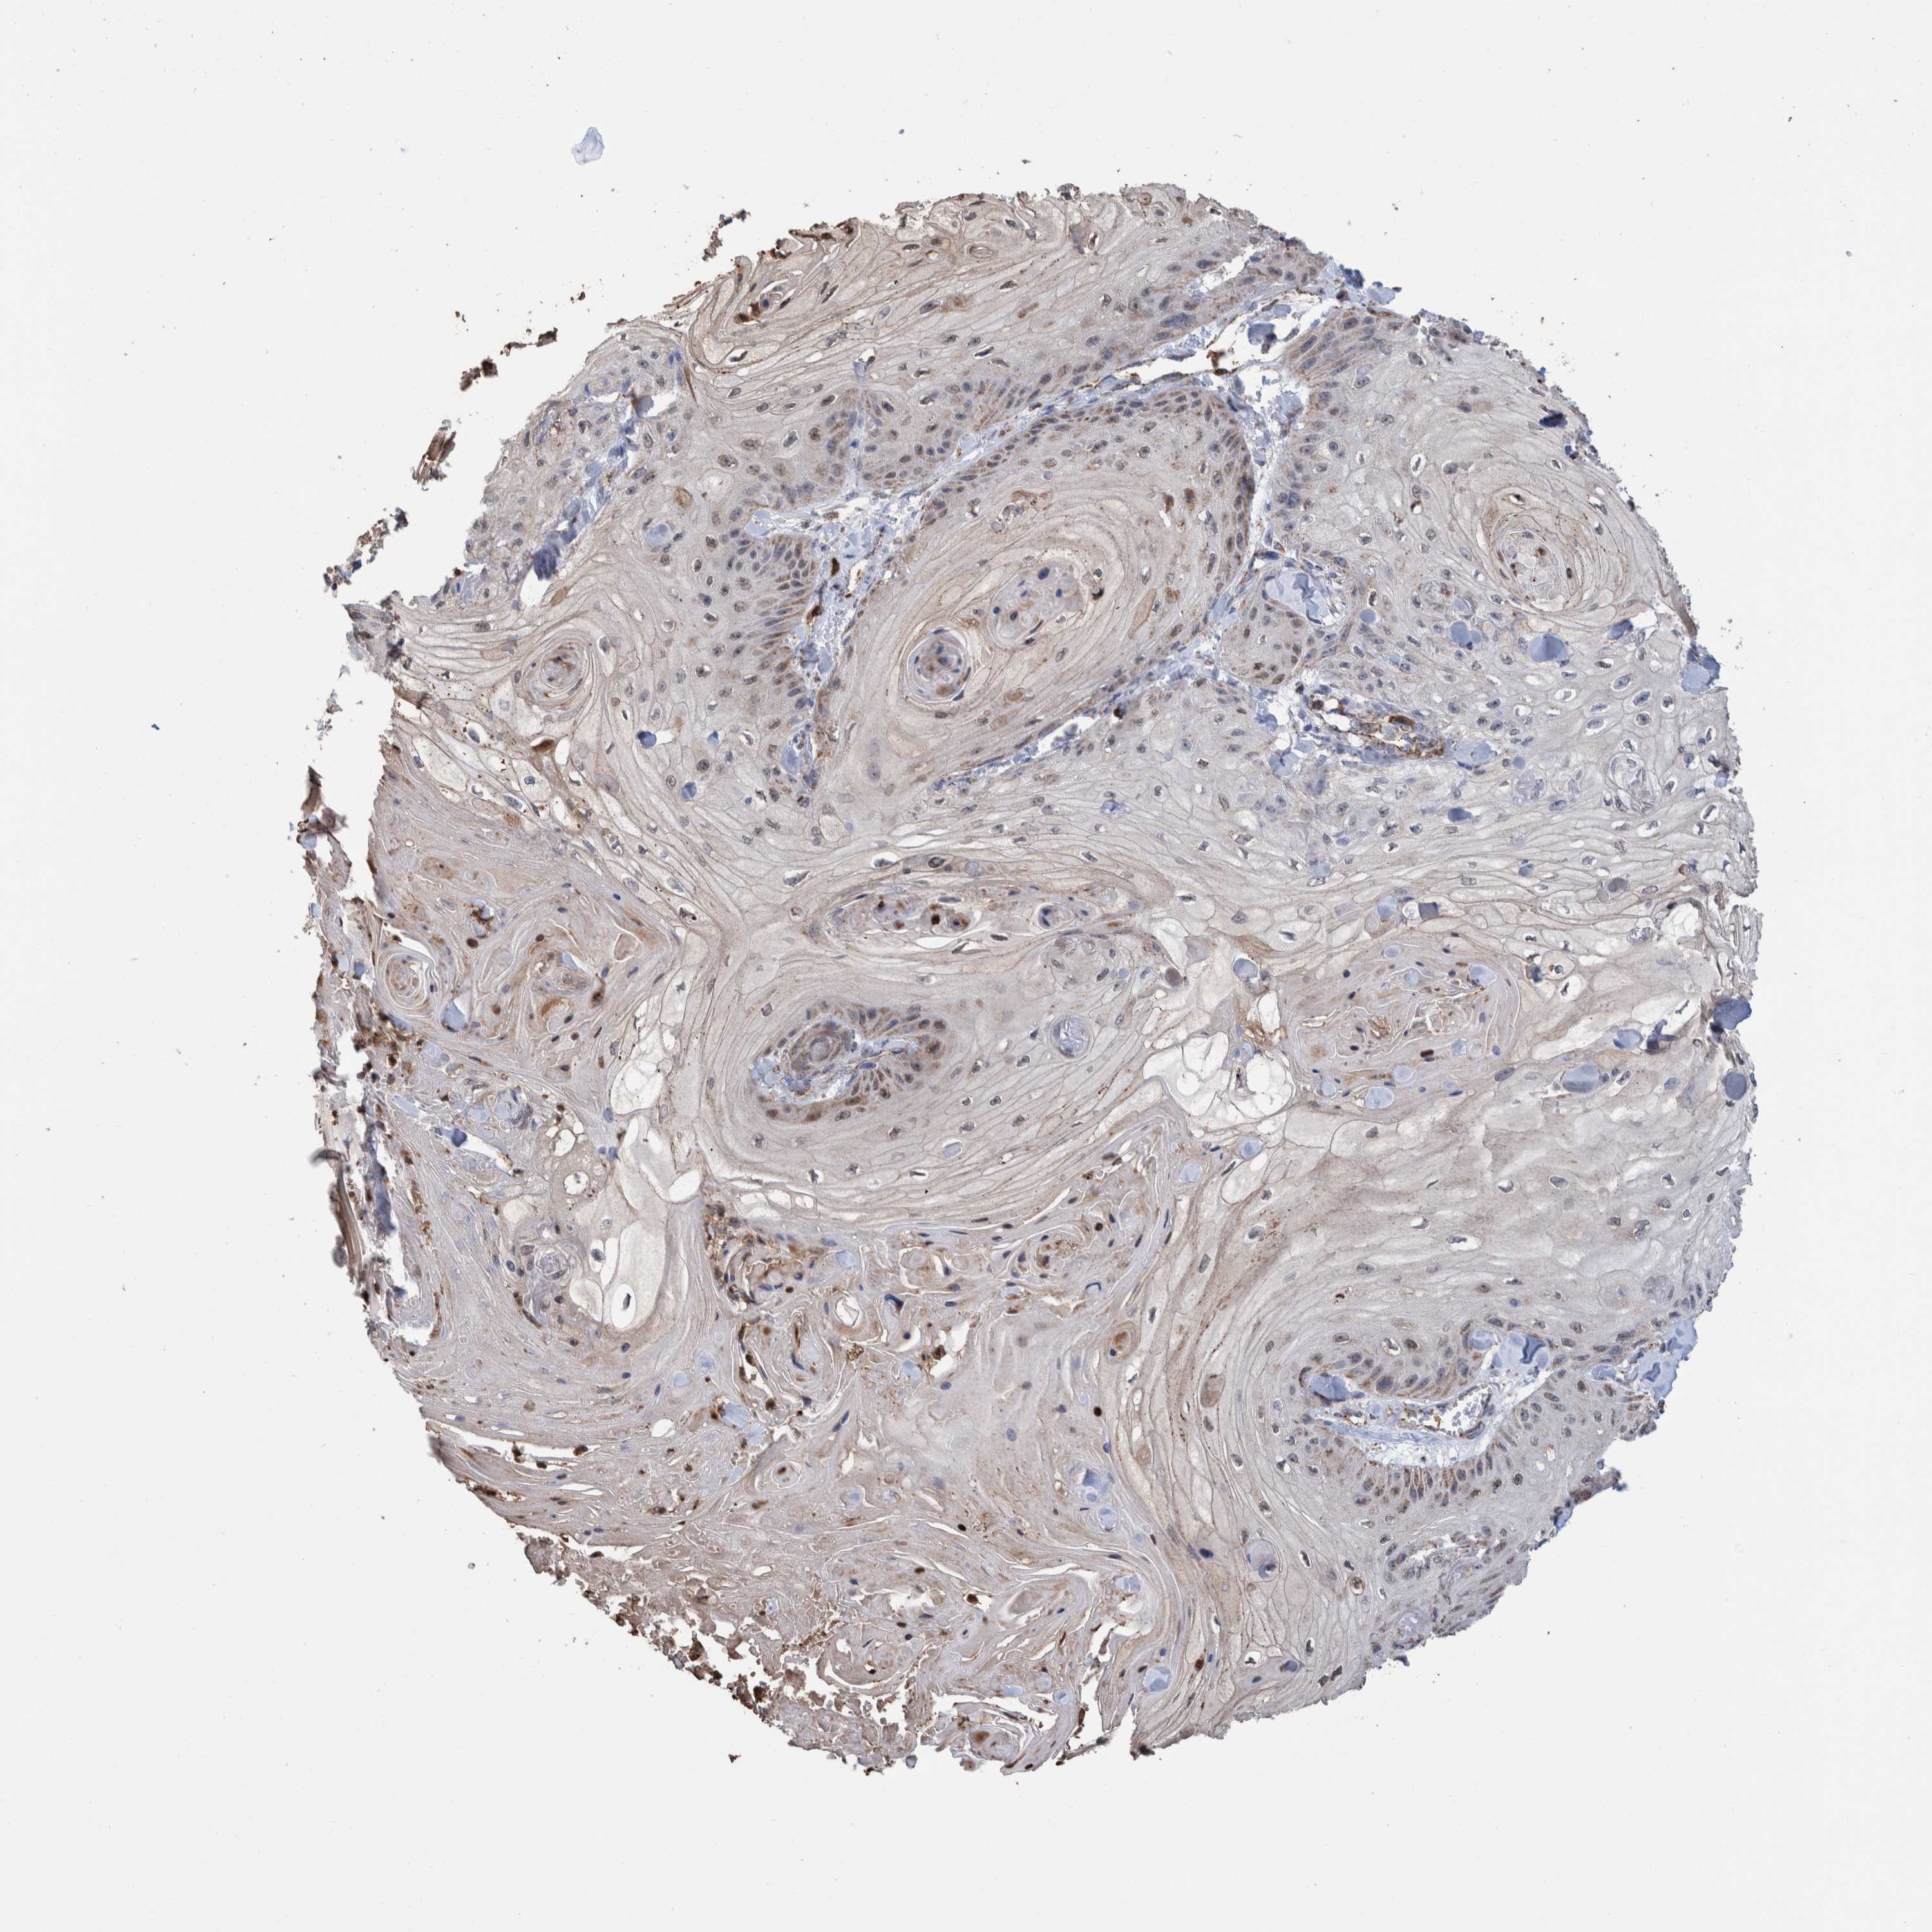

SKIN CANCER - Protein expressioni

A mouse-over function shows sample information and annotation data. Click on an image to view it in a full screen mode. Samples can be filtered based on level of antibody staining by selecting one or several of the following categories: high, medium, low and not detected. The assay and annotation is described here.

Antibody staining in the annotated cell types in the current human tissue is reported as not detected, low, medium, or high, based on conventional immunohistochemistry profiling in selected tissues. This score is based on the combination of the staining intensity and fraction of stained cells.

Each image is clickable and will lead to virtual microscopy that enables deeper exploration of all samples and also displays staining intensity scores, fraction scores and subcellular localization as well as patient and tissue information for each sample.

Antibody HPA023162

Squamous cell carcinoma, NOS